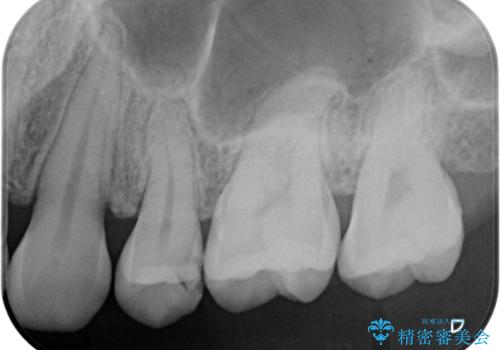

- 食事の度に物が挟まるとのことで来院された患者様です。

目視でも欠損が認められ、レントゲン写真からもむし歯が認められる状態でした。

患者様と相談の上、セラミックインレーで精密な修復治療を行うこととしました。